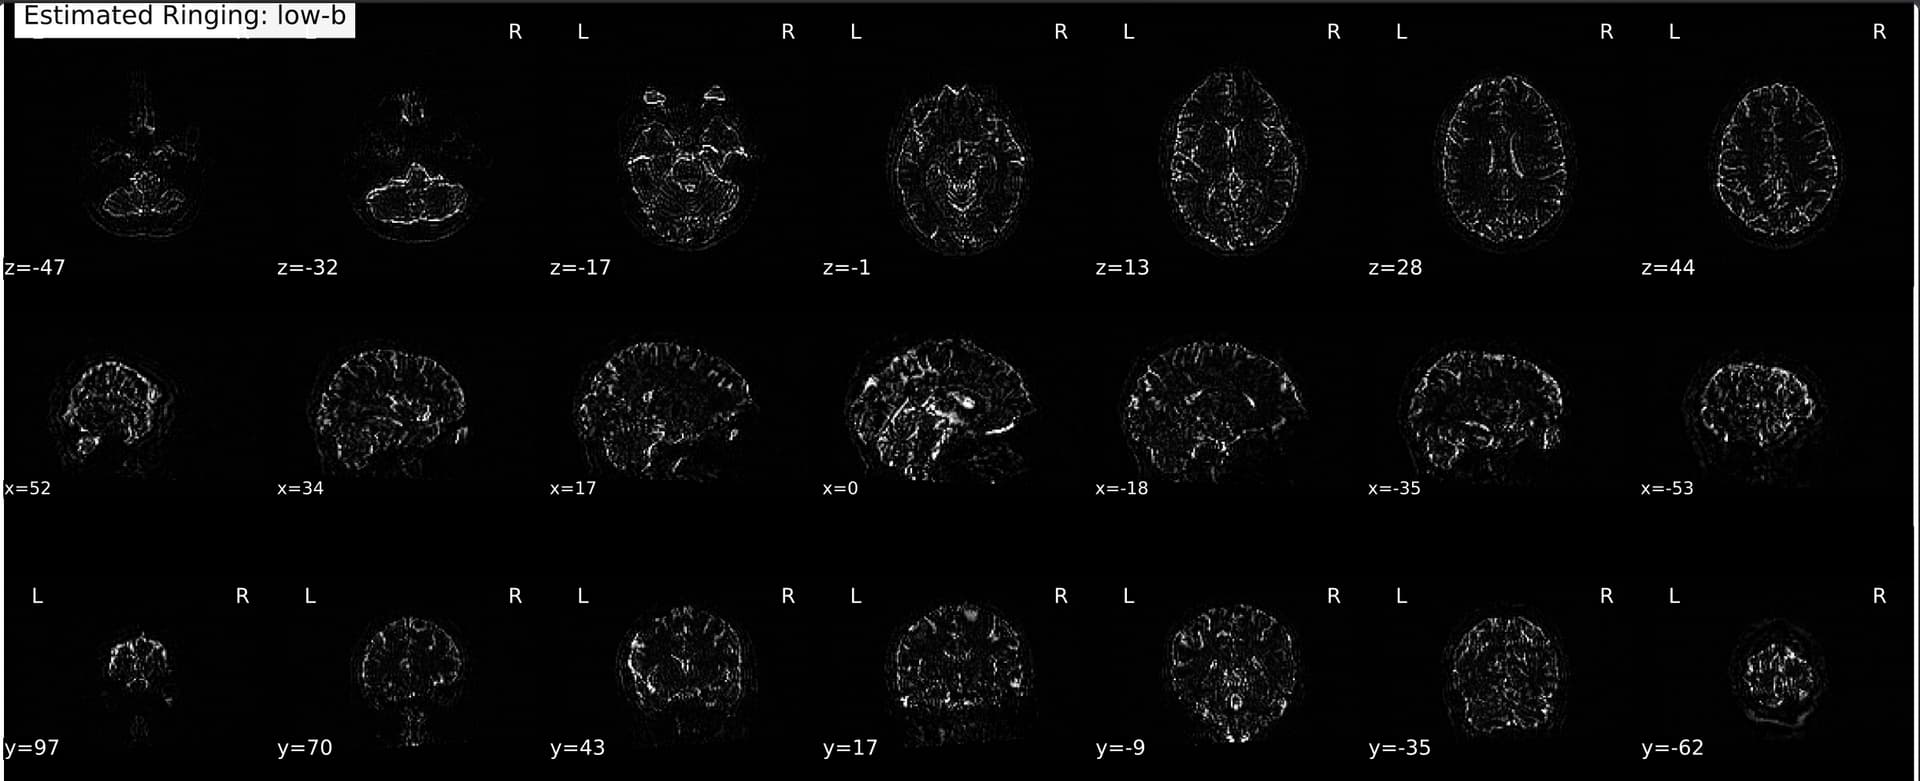

Waiting on the full pipeline to run so I can compare the final outputs, but for now, definitely looks like it’s an RPG issue.

Here’s an example cs-DSI collected at UCSB:

A Q4 also at UCSB:

And the same sequence but collected at another site:

Much more like what I’d expect! I suppose the (extremely loaded) question at this point is just whether mrdegibbs is appropriate to use for PF DSI data. I know it was designed for full-Fourier acquisitions, but from what I’m reading it’s probably ok? Also have been working with neuroimaging data long enough to know that there is rarely a straightforward answer as to what the ‘best’ preprocessing methods are haha, but I assume some Gibbs unringing is probably preferable to none, and mrdegibbs at least seems to provide something more sensible.